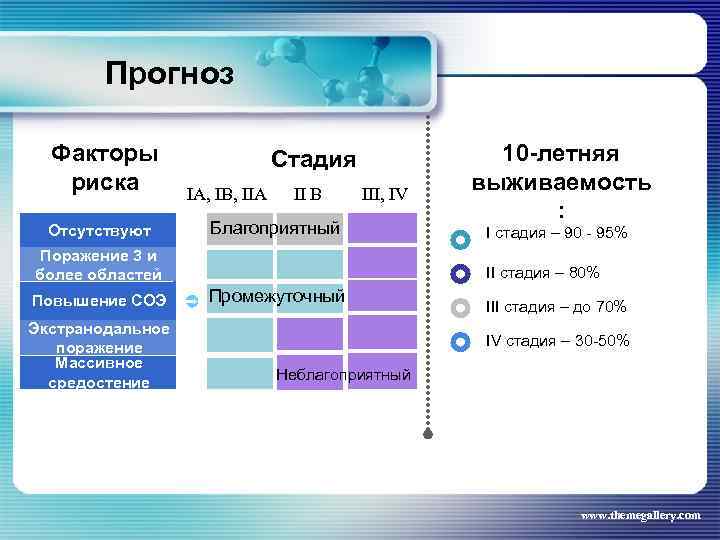

Прогноз Факторы риска Отсутствуют Стадия IA, IB, IIA II B III, IV Благоприятный Поражение 3 и более областей Повышение СОЭ Экстранодальное поражение Массивное средостение 10 -летняя выживаемость : I стадия – 90 - 95% II стадия – 80% Промежуточный III стадия – до 70% IV стадия – 30 -50% Неблагоприятный www. themegallery. com

Прогноз Факторы риска Отсутствуют Стадия IA, IB, IIA II B III, IV Благоприятный Поражение 3 и более областей Повышение СОЭ Экстранодальное поражение Массивное средостение 10 -летняя выживаемость : I стадия – 90 - 95% II стадия – 80% Промежуточный III стадия – до 70% IV стадия – 30 -50% Неблагоприятный www. themegallery. com